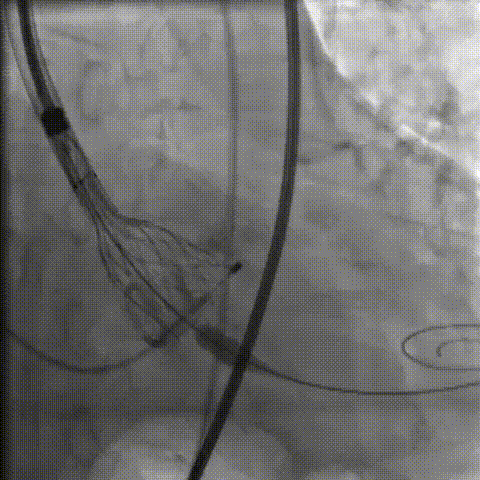

手术影像记录

主动脉根部造影

18mm球囊预扩

零位定位逐步释放至工作位,多角度评估位置良好

缓慢脱钩至完全释放,最终植入位置理想